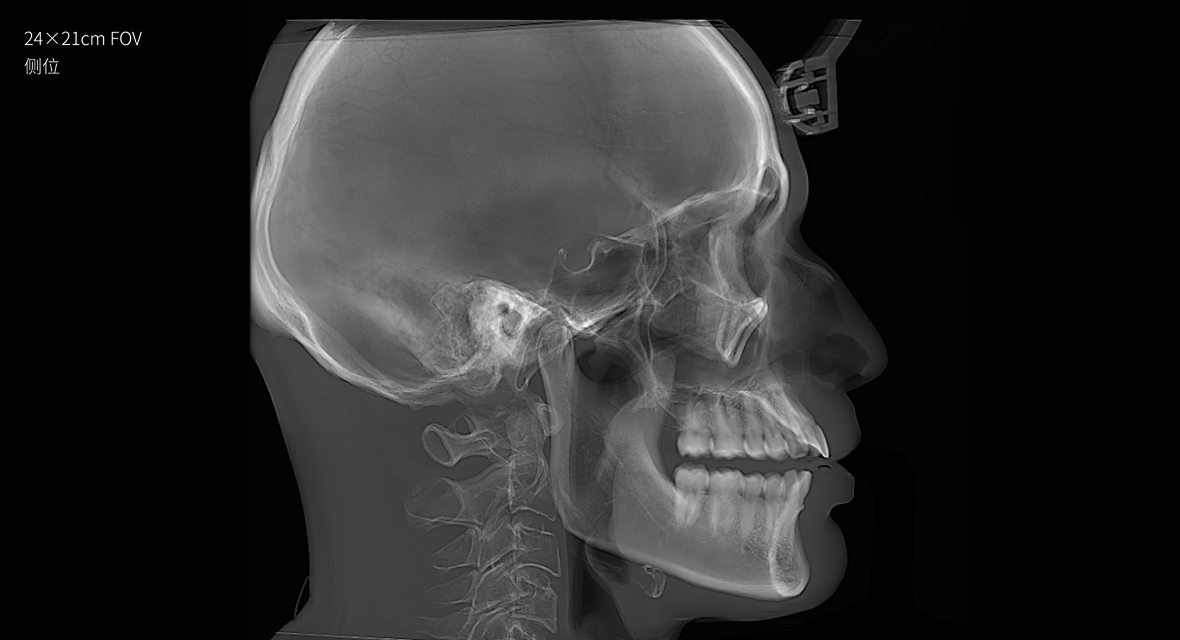

视野最大可至24×21cm

视野最大可至24×21cm,即使对于体型偏胖、脸型较大的患者,也都游刃有余。多种视野范围可供临床选择:24×21cm、16×13cm、5×5cm。

24×21的视野,可以完全覆盖患者上至额顶、下至颈角部位,前至鼻尖的范围